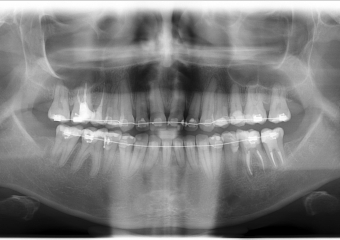

Rx Panorâmico Inicial